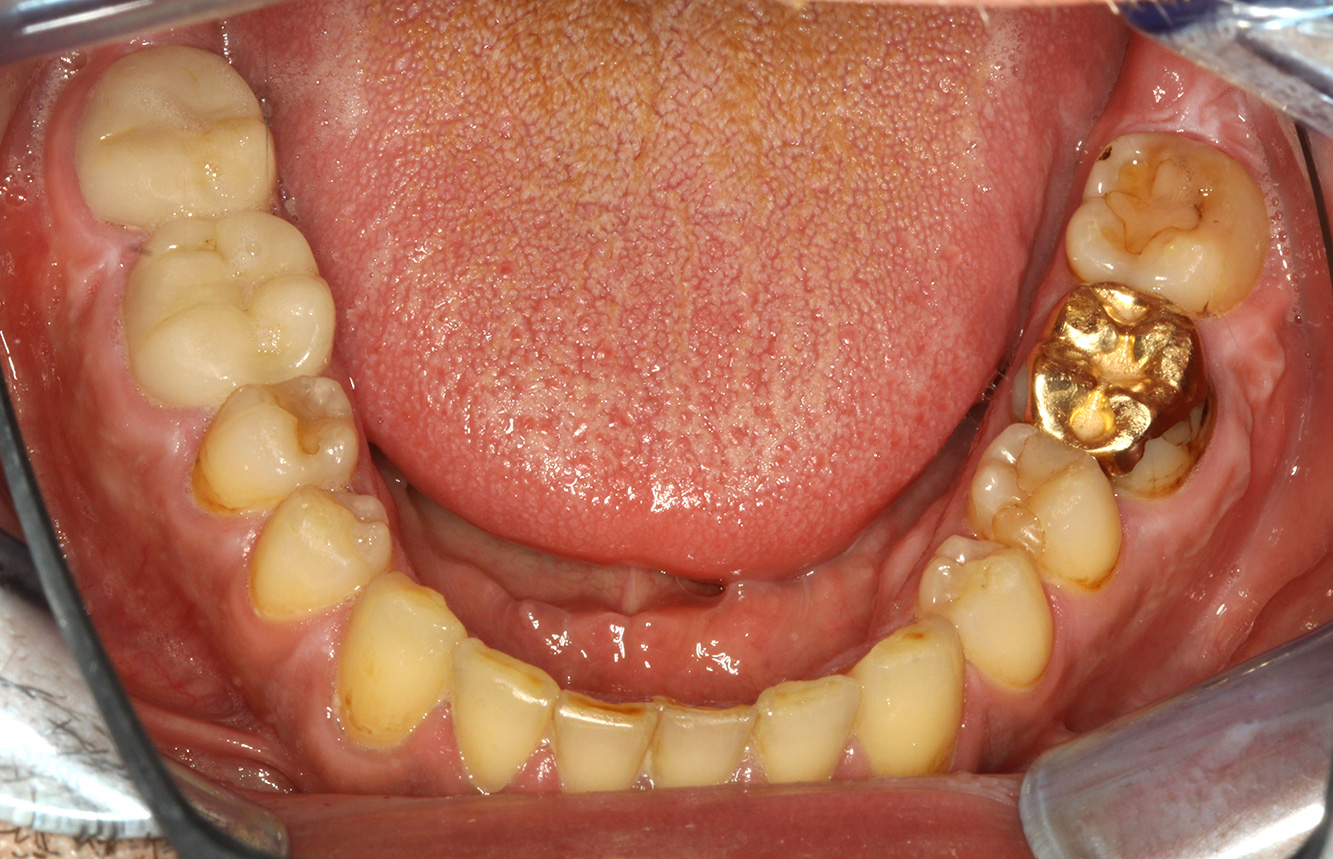

The patient is 39 years old and has previously undergone aortic valve replacement due to valve failure and endocarditis. ASS 100 is taken regularly as an anticoagulant. In terms of lifestyle, the patient’s diet is classified as caries-promoting due to the regular consumption of sugary foods and the fact that six to seven meals are consumed daily. The patient’s oral health indicates a moderate risk of caries, with active lesions. The risk of periodontitis is low, but gingivitis is present. The following recommendations are made for prophylactic treatment.

No specific instrument recommendations can be determined for the prophylaxis session. Targeted application of air and rotary polishing can be used to gently reduce plaque and stains on the restoration edges, and to reduce recolonization niches for cariogenic bacteria (19).

Fluoridation is recommended to further support the prevention of caries, and especially to prevent new formation around the restoration edges, and to seal the root surfaces. Both of these measures can reduce the teeth’s sensitivity to temperature.